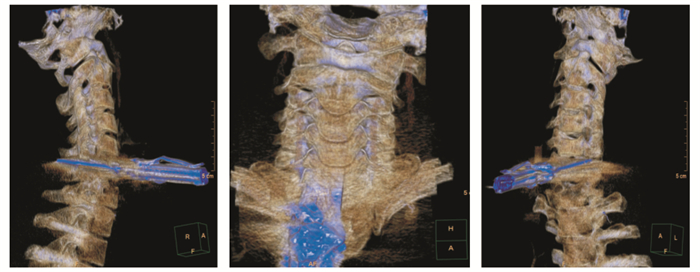

|

| 图 3 患者颈部三维立体重建结果 |

|

|

|

(2) 气管损伤:无呼颈吸困难和喘鸣,无发绀、无咯血,无声音嘶哑,未触及颈部伤口漏气及皮下气肿。颈部三维立体重建提示(图 3):患者椎体被完全穿透。